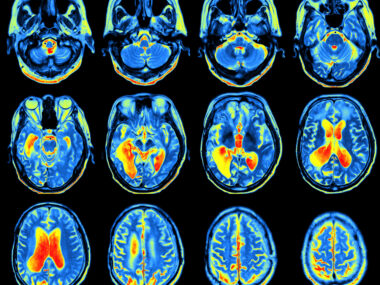

Parkinson’s is caused by abnormalities in dopamine signaling in the brain. DaT-SPECT is an imaging technique that uses X-rays and an injected dye to visualize dopamine activity in the brain. It is considered helpful in diagnosing Parkinson’s — particularly for differentiating between true Parkinson’s disease, and other conditions that may result in Parkinson’s-like symptoms.